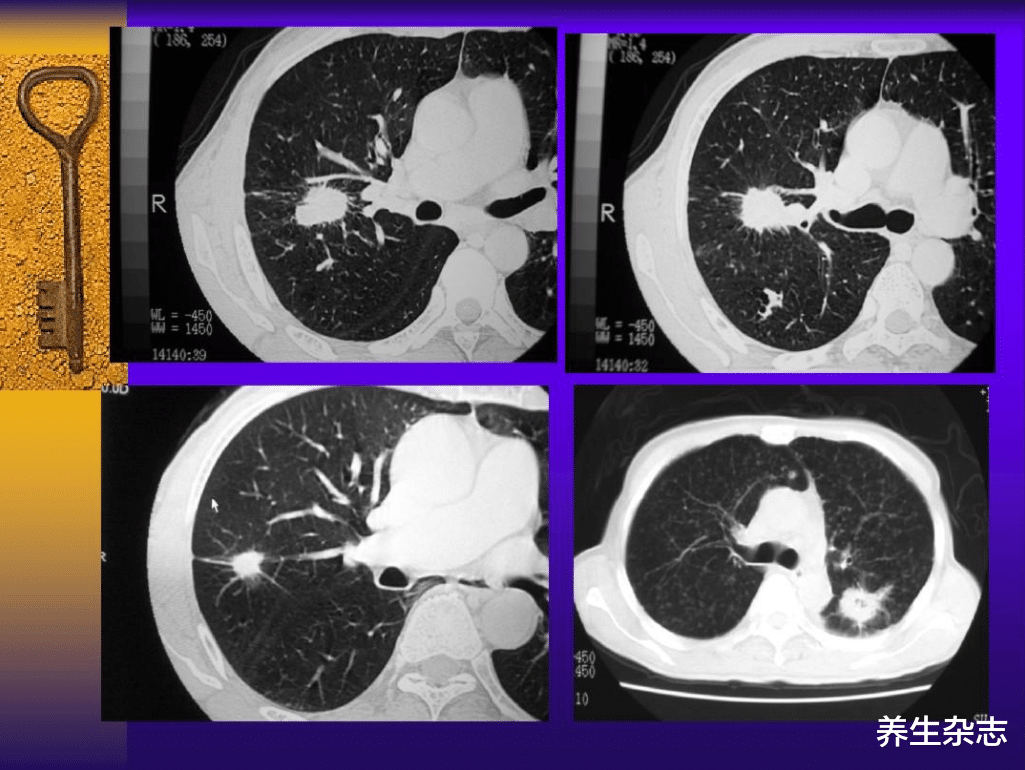

经过腰椎和肺部的检查 , 发现肺癌 , 胸腰椎多发骨转移 。 检查肺部的 CT片 , 这是一个实性结节 , 2.8厘米 , 贴近肺叶间的叶间胸膜 。 在接近胸膜或较粗的肺血管(中轴间质)时 , 实性结节若为恶性 , 则有早期转移的危险 。

这种情况就是王大爷 , 癌细胞沿胸膜脉管扩散 , 至胸椎、腰椎内发生转移 , 从图片可以明显看到 , 脊椎骨被癌细胞咬出很好孔洞 。